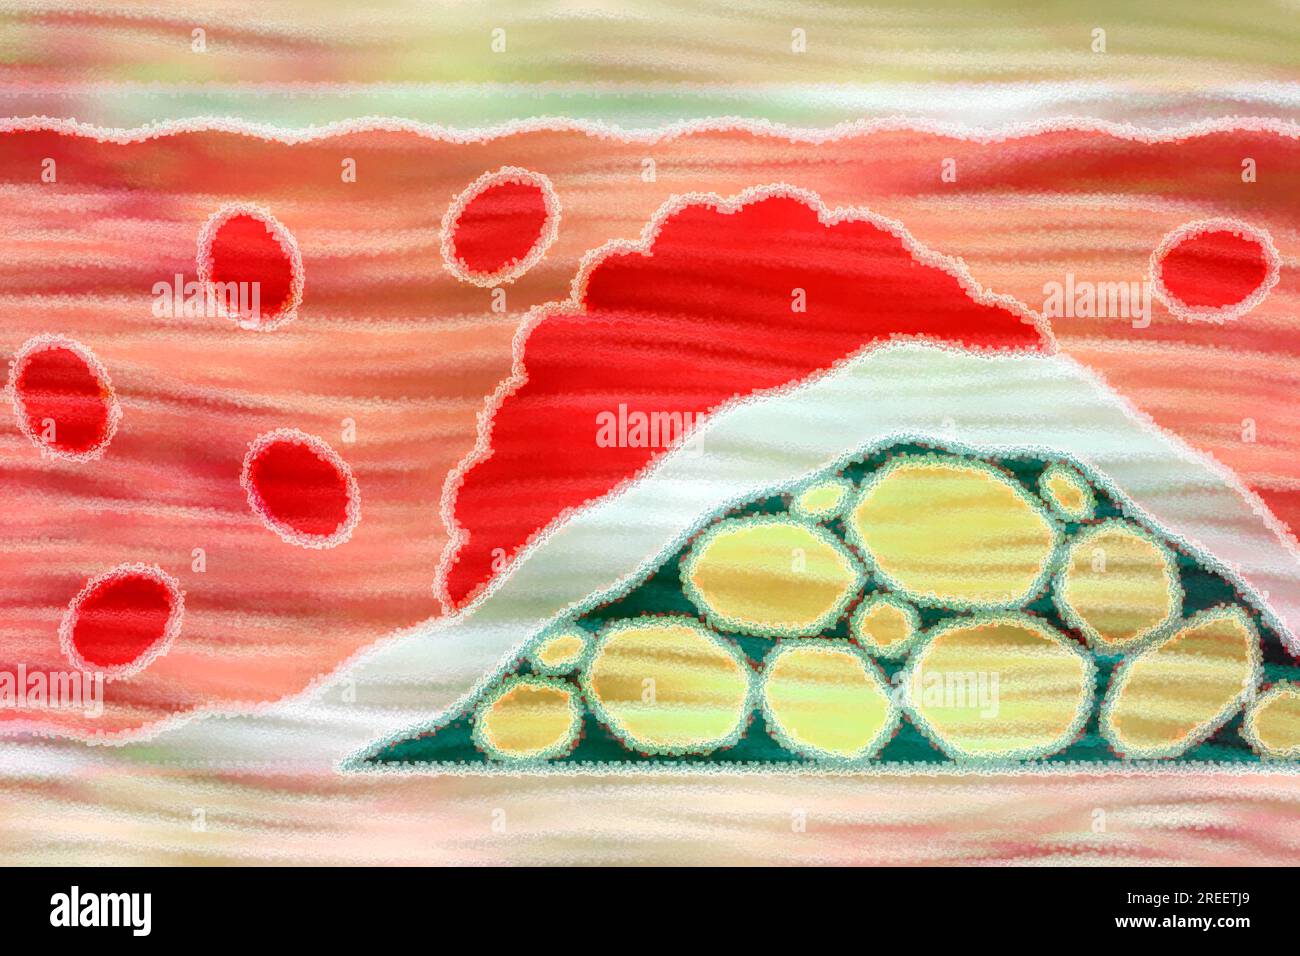

Arteriosclerosis is a common vascular disease in which the arteries become narrowed and hardened by deposits such as fats Stock Photohttps://www.alamy.com/image-license-details/?v=1https://www.alamy.com/arteriosclerosis-is-a-common-vascular-disease-in-which-the-arteries-become-narrowed-and-hardened-by-deposits-such-as-fats-image559663617.html

Arteriosclerosis is a common vascular disease in which the arteries become narrowed and hardened by deposits such as fats Stock Photohttps://www.alamy.com/image-license-details/?v=1https://www.alamy.com/arteriosclerosis-is-a-common-vascular-disease-in-which-the-arteries-become-narrowed-and-hardened-by-deposits-such-as-fats-image559663617.htmlRF2REETJ9–Arteriosclerosis is a common vascular disease in which the arteries become narrowed and hardened by deposits such as fats